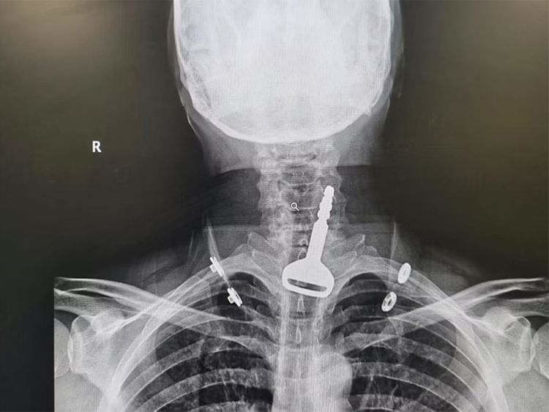

Σύμφωνα με το Gulf News, ο 49χρονος άνδρας εισήχθη στα επείγοντα του νοσοκομείου, όπου το προσωπικό παρατήρησε ότι είχε δυσκολία στην αναπνοή. Οι ακτινογραφικές εξετάσεις έδειξαν ένα κλειδί αυτοκινήτου μέσα στην αναπνευστική οδό και ο ασθενής είπε στους γιατρούς ότι το κατάπιε κατά λάθος ενώ έπαιζε με αυτό. Αποφασίστηκε ότι μια ενδοσκόπηση για την αφαίρεση του κλειδιού και την άρση της απόφραξης των αεραγωγών ήταν η καλύτερη λύση, αλλά το γεγονός ότι ο άνδρας ήταν καρδιοπαθής έκανε τη διαδικασία πολύ πιο περίπλοκη.